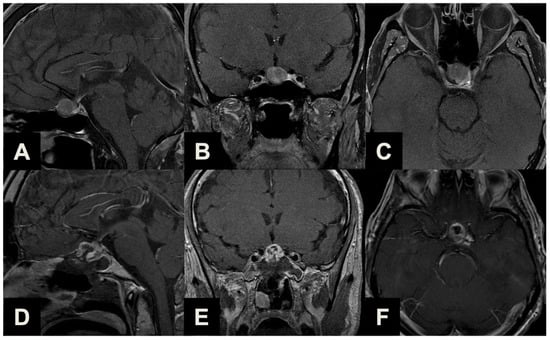

| Type 1 | Ectopic peduncular or supradiaphragmatic peri-infundibular PAs, including ectopic microadenomas of the pituitary stalk or purely supradiaphragmatic macroadenomas (mostly remnant or recurrence after previous partial surgeries). These tumors are not suitable for an EEA because they have no sellar infradiaphragmatic component. |

| Type 2 | PAs with sub-frontal extension, including macroadenomas with a supra- or infradiaphragmatic sub-frontal extension. These tumors are not fully resectable with an EEA because of their sub-frontal component, which extends anteriorly with an unfavorable angle and direction for the trans-sphenoidal approach. |

| Type 3 | PAs presenting with a major extrasellar component, including macroadenomas with suprasellar supradiaphragmatic component exceeding the sellar volume (i.e., air balloon PAs) unlikely to be delivered through the sella with an EEA, and macroadenomas with both a large intrasellar infradiaphragmatic part and a large suprasellar supradiaphragmatic portion connected through a narrow isthmus (i.e., snowman PAs), which impairs their resection through an EEA. |